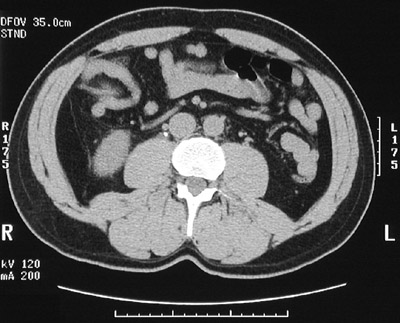

| These two abdominal CT scan views show a calyceal calculus within the left kidney. In the view below, a tiny calculus is seen in the region of the mid-right ureter. Straining the urine to catch the stone can be done so that the stone can be sent for chemical analysis. Determination of the cause for urinary tract calculi can help to provide treatment to prevent the calculi becoming a "renewable natural resource." |